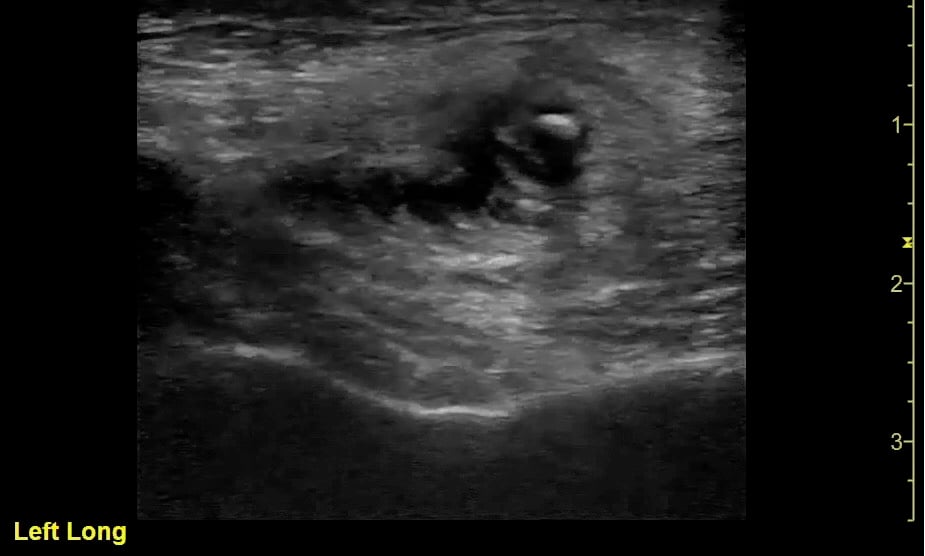

- Comparison of Sialadenitis on the left and normal submandibular gland on right:

- Figure 21. Sialadenitis (left) vs normal (right)